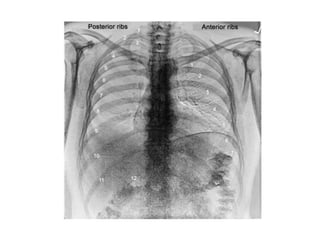

a. Inspiration

 The diaphragm should be found at about the

level of 9 - 10th posterior rib or 5 - 6th anterior rib

on good inspiration

IN PA VIEW:-

 Clavicles don’t project too high into the apices or

thrown above the apices (more horizontal)

 Heart wont be magnified over the mediastinum

therefore preventing the appearance of

cardiomegaly

 Scapula are away from the lung fields

 Ribs are obliquely oriented in PA view

 Spine and posterior ends of ribs are clearly seen